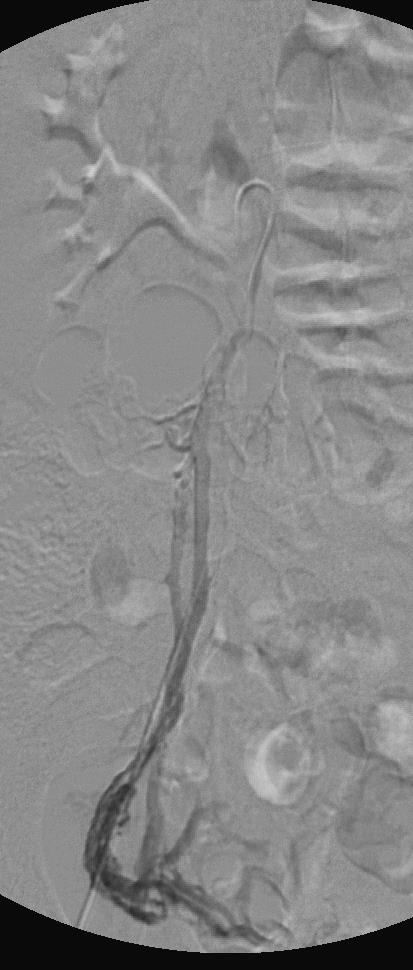

介入联合治疗是指 1. 不同栓塞材料的联合应用 2. 多静脉的联合栓塞 3. 介入治疗+ 不同栓塞材料的联合治疗(E. Aksungur cirse 2015) 1. 器械栓塞 vs 器械栓塞+化学硬化治疗 评价标准:VAS;questioning nine items according to SIR recommendations 结果:双侧栓塞41(45%),左侧栓塞38(42%),右侧栓塞12(13%) Bilateral ovarian vein insufficiency and pelvic varicous veins

总VAS中位值下降35到8(p<0.0001) 随访期间,临床改善 97.9%,剩余2% 临床稳定 机械栓塞 vs 机械+化学硬化 没有显著意义,临床改善 (p=0.87)

疾病相关症状(all disease-specific symptoms)p<0.0001 没有操作相关严重并发症 结论: 血管栓塞对于治疗盆腔充血综合征是安全和有效的治疗方法。当比较联合机械+化学硬化治疗时,尽管缺乏优效性,但在血管内栓塞的治疗选择中,机械性栓塞应该成为优选的方法,因为较短的操作时间和较低的放射剂量。 |